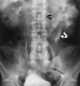

Congenital ureterectasis

Hydroureter